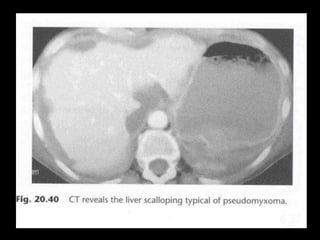

Pseudomyxoma peritonei (PMP) is a rare condition characterized by gelatinous ascites resulting from the rupture of appendiceal mucinous tumors, leading to significant abdominal complications. The incidence is approximately 2 cases per million per year, with a predominance in females, and diagnosis often relies on imaging techniques like ultrasound and CT scans. Effective treatment involves cytoreductive surgery combined with hyperthermic intraperitoneal chemotherapy (HIPEC) to manage disease progression and improve outcomes.